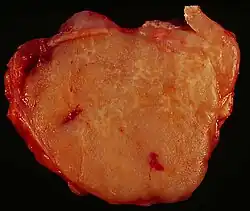

Die Diagnose wird histologisch anhand der Biopsie eines betroffenen Lymphknotens gestellt. Neben der histomorphologischen Beurteilung werden spezielle Färbetechniken angewandt, um das gewonnene Biopsiematerial genau klassifizieren zu können. Die derzeit gültige WHO-Klassifikation hat die früher verwendete Kiel- beziehungsweise R.E.A.L.-Klassifikationen (Revised European-American Classification of Lymphoid Neoplasms) weitestgehend abgelöst.